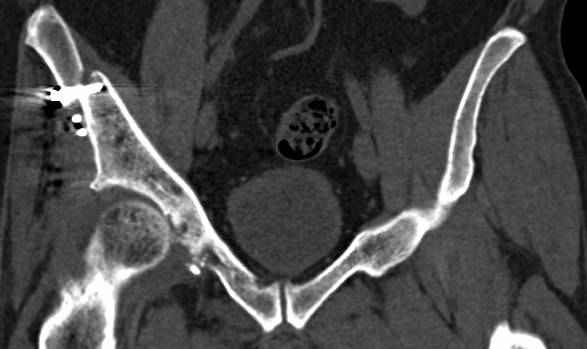

Интересно было бы посмотреть рентгенограммы до операции. У меня впечатление, что я не все вижу, что тут есть... Уважаемые Господа "тазисты" и "тазологи", к какому типу переломов вертлужной впадины по Летурнелю вы бы отнесли это случай?

Из переломов проходящих через крыло и/или заднюю стенку ни простой перелом "передней колонны" (явно имеется пером задней стенки, и не видно перелома седалищной или лонной), ни простой "поперечный", ни ассоциированный "Т-образный" (т.к есть перелом крыла и не видно перелома седалишной), ни ассоциированный "задняя колонна+задняя стенка", на ассоциированный "поперечный+задняя стенка", ни ассоциированный "передняя колонна+задняя гемисфера" (не видно перелома седалищной), ни ассоциированный "обе колонны" (не видно перелома лонной седалищной) не подходят под эту классификацию....

к таковым себя не причисляю, но...обычное дело для нашей страны - выкладывать 3D и не показывать стандартные проекции Judet. Дигност представляет те ракурсы, которые по-его мнению наиболее информативны, более того комп сам достраивает какие-то мелкие повреждения по 3D по своему усмотрению. По данной реконструкции можно предполагать высокий двухколонный перелом с оскольчатыми передней и задней колоннами, оскольчатую высокую переднюю колонну с задним полупоперечником или одно из перечисленных с вовлечение КПС. У меня впечатление за второй вариант, но нужно обследовать нормально - проекции, сканы.

высылаю дополнительно сканы.